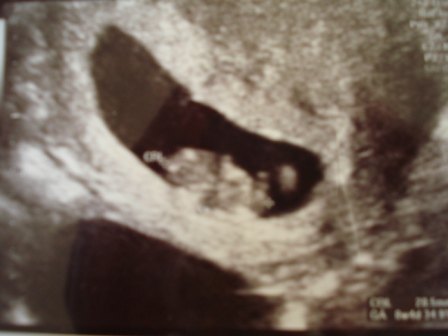

Så er vi lige kommet hjem fra en tryghedsscaning på en klinik i Hobro.. Det er ski mange penge for så lidt - men har fået ro da, da jeg jo så hjerteblink så det var dejligt - plus hun så sagde at når dette var set, så var der 97 % chance for den blev der

Vedhæftede fotos (klik for at se i fuld størrelse)